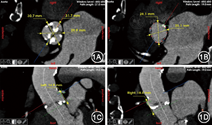

患者男性,85岁,因"发作性胸闷、气短4年,加重2 d",于2014年5月15日入院。查体:心率76次/min,血压135/85 mmHg(1 mmHg=0.133 kPa),双肺呼吸音清,心律齐,胸骨左缘第3肋间可闻及4/6级收缩期喷射样杂音。门诊经胸超声心动图示主动脉瓣峰值流速5.9 m/s,峰值压差140 mmHg,平均压差71 mmHg,诊断为主动脉瓣重度狭窄并轻度关闭不全。冠状动脉和主动脉增强CT示冠状动脉左前降支、左回旋支、右冠状动脉散在钙化,左前降支中段混合斑块,局部狭窄约50%;主动脉瓣瓣叶增厚、钙化。CT测量经导管主动脉瓣置入术(transcatheter aortic valve implantation,TAVI)的部分参数如下:主动脉瓣环直径23.1 mm×28.1 mm,主动脉窦部直径28.9 mm×31.7 mm,右冠状动脉开口距窦底18.0 mm,左冠状动脉开口距窦底14.9 mm,升主动脉直径31.0 mm(图1)。CT检查的DICOM图像即刻导入Fitme软件(飞特图盟北京科技有限责任公司),通过图像分割、三维化、剪裁、平滑、修饰等计算机辅助图像处理,生成可以打印的三维图形文件。然后连接国产3D打印机(杭州先临三维科技股份有限责任公司)进行打印,打印材料左心室及大部分主动脉采用红色塑料,主动脉根部采用透明树脂材料(图2,图3,图4)。